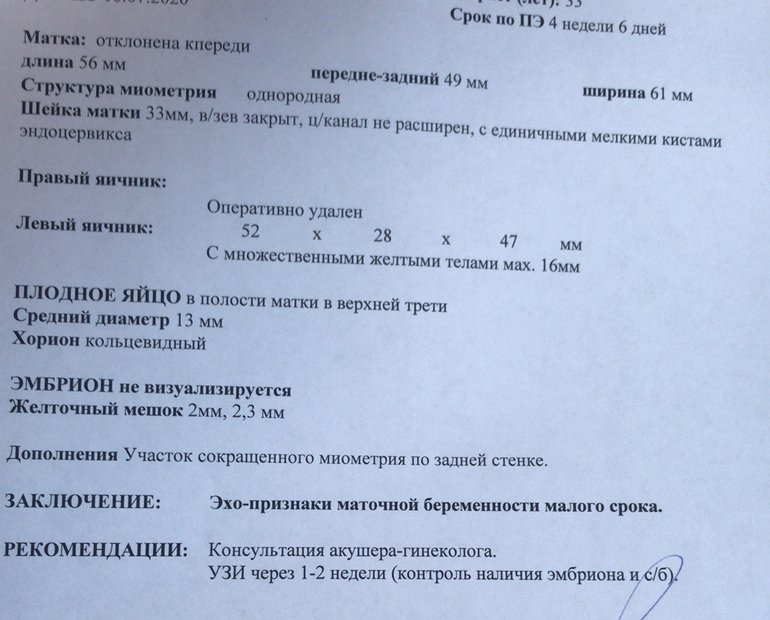

Расшифруйте узи🙏

Что означает: в полости матки в верхней третьей

Участок сокращённого миометрия

Матка отклонена кпереди